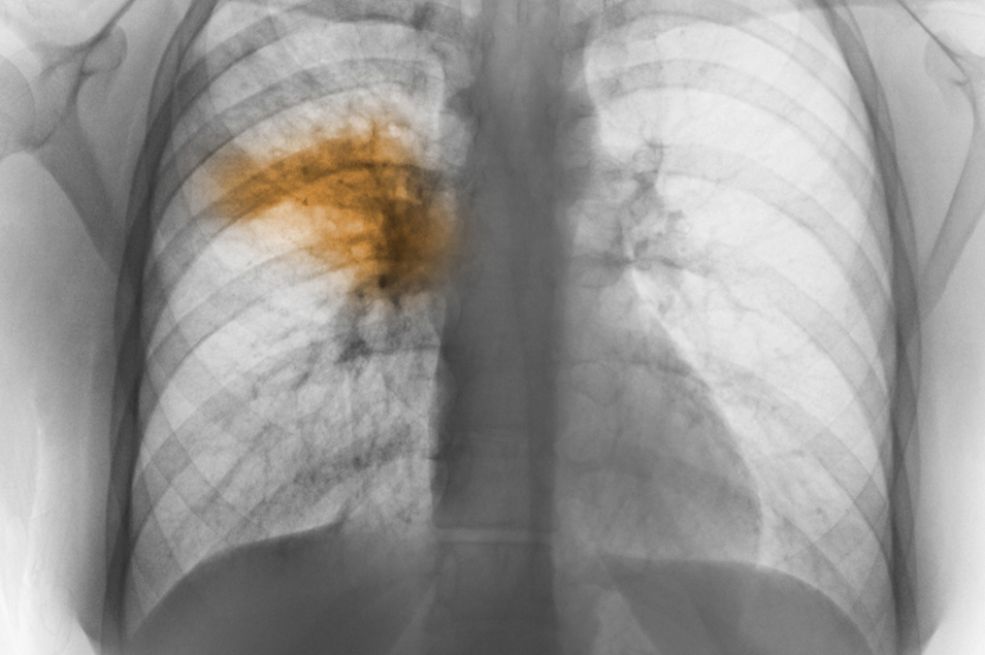

Upala pluća ili pneumonija je akutna infekcija plućnog tkiva uključujući alveolarne prostore i prostor između alveola, tzv. intersticij. Uzrokovana je jednim od brojnih mogućih uzročnika: bakterijama, virusima, gljivicama, a može nastati i udisanjem (aspiracijom) prašine, kemijskih iritansa, hrane ili povraćenog sadržaja. Liječenje upale pluća obično uključuje antibiotike ako je bakterijska infekcija uzrok, odmor, unos dovoljno tekućine i terapiju za olakšavanje simptoma. U težim slučajevima, hospitalizacija može biti potrebna, posebno kod osoba s oslabljenim imunološkim sustavom, starijih osoba i onih s drugim kroničnim zdravstvenim problemima, piše poliklinika-binova.hr.

Iako je povišena tjelesna temperatura (vrućica) čest simptom upale pluća, postoji mogućnost da se upala pluća javi bez značajnog porasta temperature. Ovo je poznato kao “tiha” ili “bez groznica” pneumonija. Ova pojava može imati nekoliko mogućih uzroka i značajnih aspekata. U nekim slučajevima, tijelo pacijenta može reagirati na infekciju pluća tako da ne izazove izraženu povišenu temperaturu. Ovo se može dogoditi ako je imunološki sustav već aktivan i učinkovito reagira na infekciju. Također, nekim slučajevima, blaga upala pluća ili početni stadiji bolesti mogu rezultirati manje izraženom vrućicom ili čak odsustvom nje.